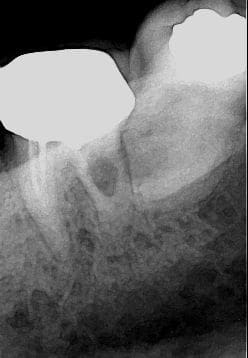

Salut à tous , que pensez vous de cette image lacunaire sur la racine distale de 37. Le bridge en place a été fait il y a pas mal de temps et ne posais pas de problème . La séparation des racines a été faite la semaine dernière ( pb. d'infiltration inter radiculaire en lingual mal visible sur la radio ) suites op. excellente et je dois refaire le brige. La patiente a 73 ans . A mon avis il ne devrais pas y avoir trop de problème mais votre avis m'interresse. A+ jacques.

ça ressemble à une résorption interne. Il me semble qu'il n'y a plus d'image de traitement de racine, comme s'il avait disparu.

Il faudrait extraire cette racine distale et l'envoyer en anapath pour savoir ce qu'il y a au milieu de cette lacune.

d'accord avec canin; image resorption interne sur la distale a extraire et si tu veux etre sur, anapath.